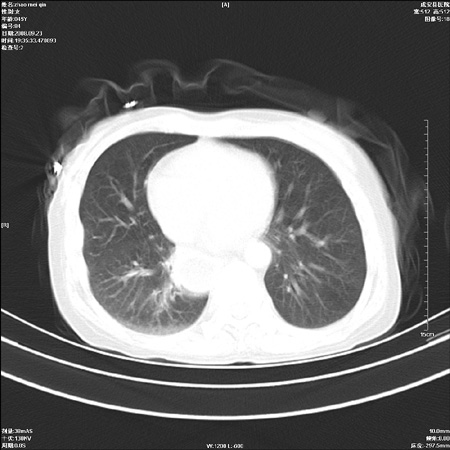

标题: CT15861:女 60 外伤后1小时 胸疼 [打印本页]

标题: CT15861:女 60 外伤后1小时 胸疼

外伤后1小时 胸疼 是外伤后引起的吗?

食道扩张明显下端逐渐变窄,倒像贲门失迟缓

非外伤性改变,典型的贲门失迟缓症

食道扩张明显下端逐渐变窄,大量食物存留,象贲门失迟缓症。